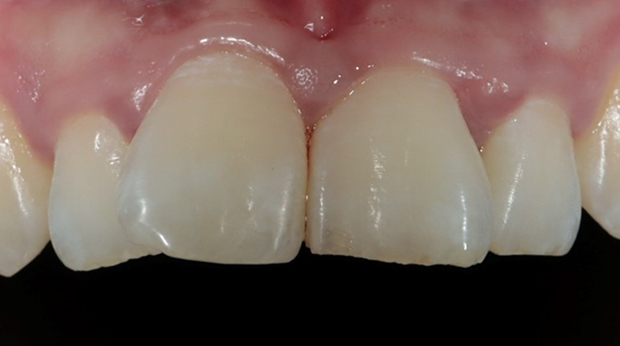

라미네이트